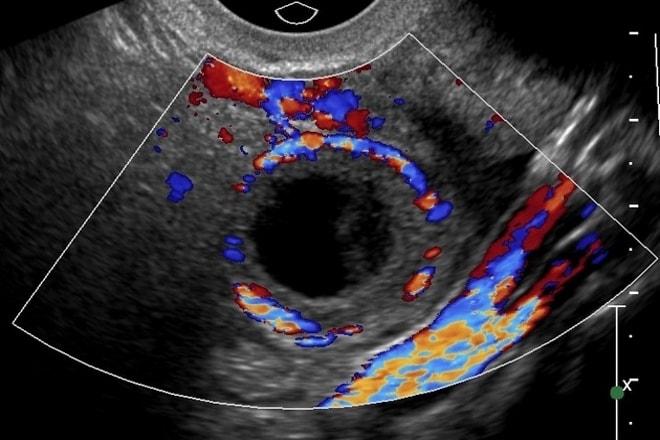

При визите к врачу в первую очередь осуществляется анализ клинической картины заболевания и изучение истории болезни пациентки. Затем проводится гинекологический осмотр на специальном кресле. Если киста небольшого размера, врач может ее не заметить. В таком случае для постановки диагноза используется ультразвуковое исследование. Этот метод позволяет выявить новообразования различных размеров, а также определить их тип, расположение и структуру. Обследование выполняется через влагалище, что дает возможность ближе подойти к яичникам и получить более детальное изображение. На экране анэхогенная киста яичника отображается как темное пятно.